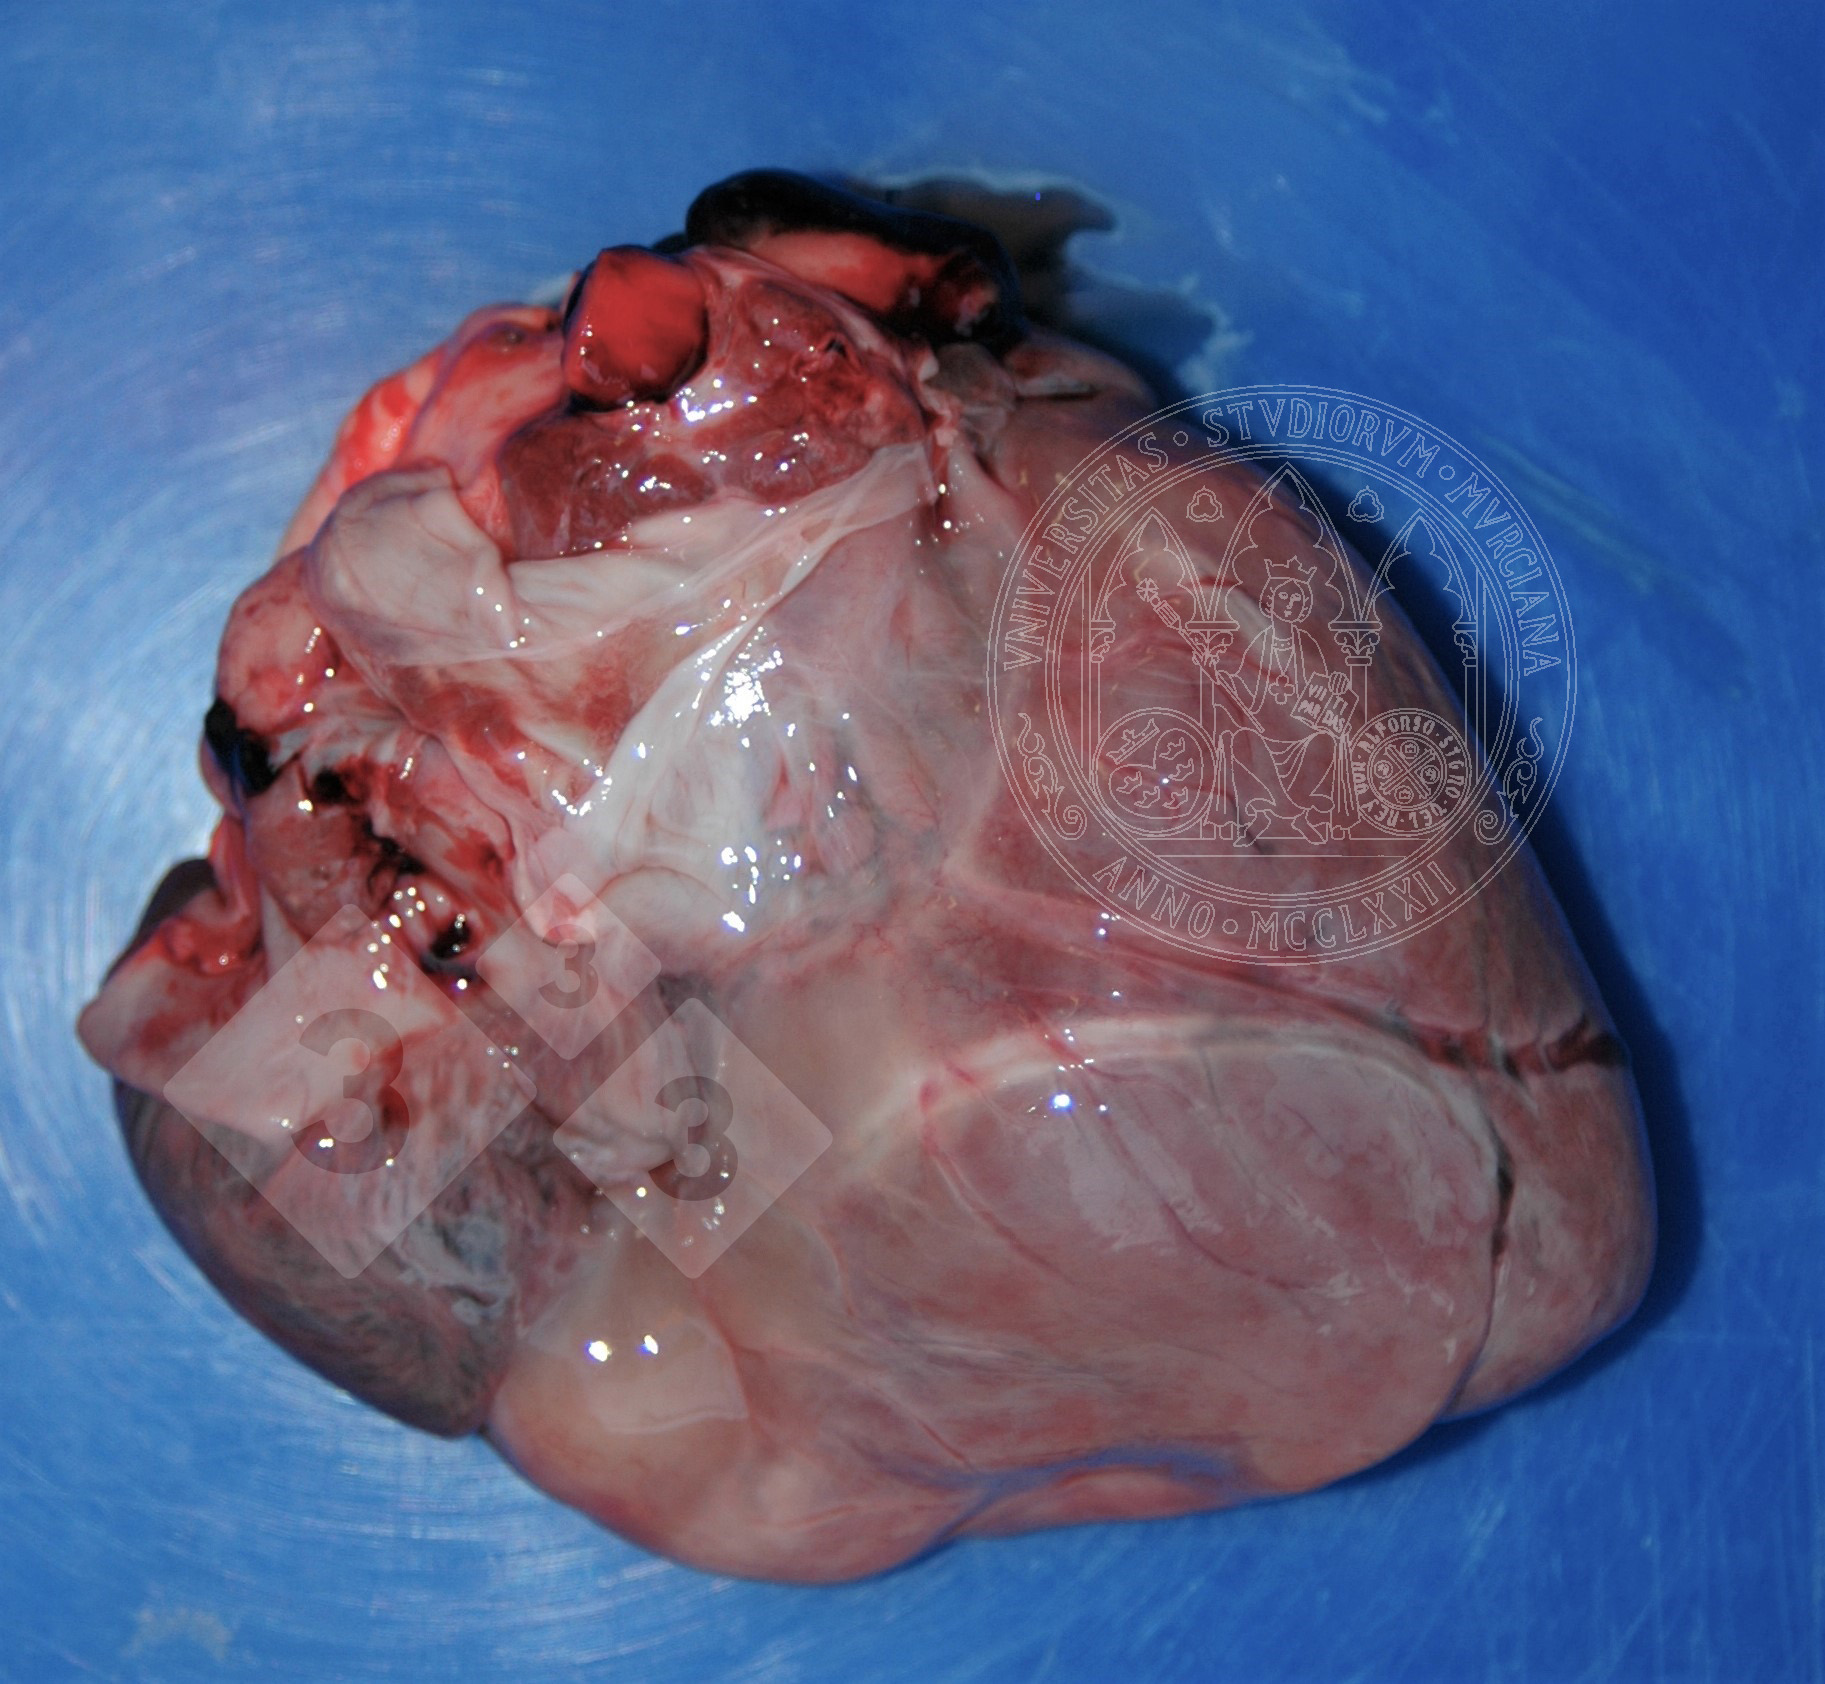

Widzimy to uszkodzenie w przypadkach wyniszczenia. Z kilku powodów może to być mobilizacja zapasów tłuszczu, na przykład z nasierdzia. Wakuole lipidowe zmniejszają rozmiar, przybierając szary, galaretowaty wygląd. Czasami widzimy małe, martwicze, plamki białego tłuszczu.

Musimy dokonać diagnozy różnicowej z obrzękiem, czy to z zakaźną etiologią, czy też nie.